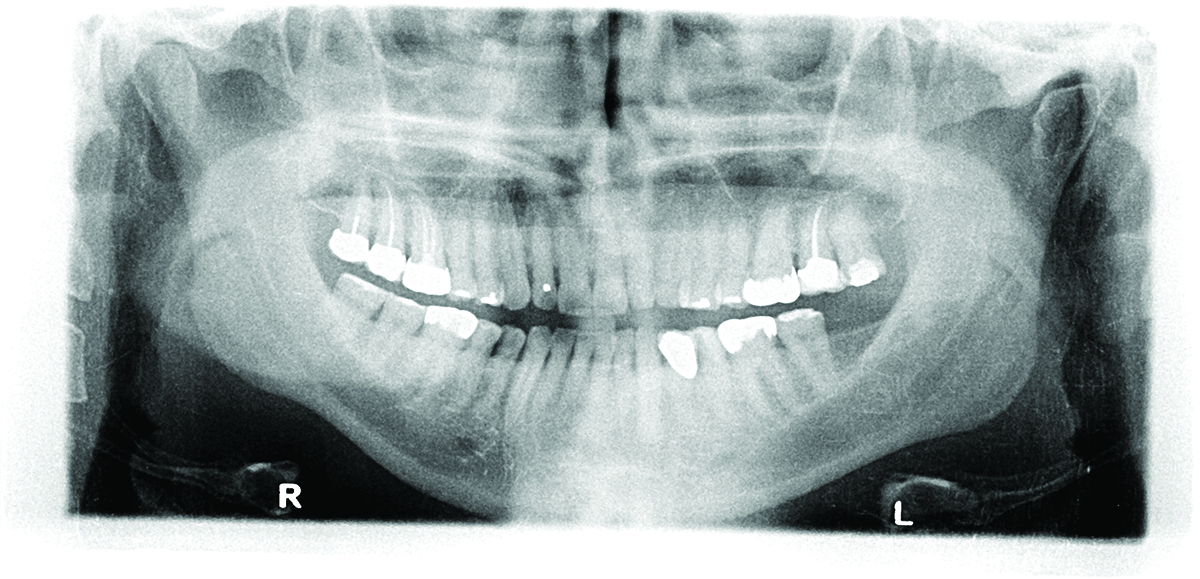

Panoramic radiograph from 2009.

Figure 6

Panoramic radiograph taken in 2017. Note increased occlusal erosion of tooth No. 18.

Figure 7

Periodontal: The periodontal examination revealed generalized clinical attachment loss but no pockets greater than 3 mm, no bleeding on probing, and no significant mobilities of any teeth. Adequate attached gingiva was present on all teeth. Home care was acceptable. Generalized tissue and bone loss was evident on the buccal surfaces of the posterior teeth. His periodontal disease was classified as stage II, generalized, grade A based on the radiographic

bone loss of more than 2 mm but less than 4 mm interdentally and the comparisons of

interdental bone level from his two panographic radiographs taken 8 years apart.

ure 4). The patient had generalized sensitivity, and tooth No. 18 was painful due to deep erosion, which approached the pulp chamber. Teeth Nos. 7 and 10 had moved out of position and rotated (Figure 5). The progression of erosion over the 8-year period could also be seen radiographically and was especially noticeable on tooth